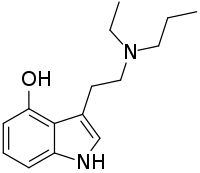

| 5-HO-MiPT | artificial | 5-OH | CH3 | CH(CH3)2 | 5-hydroxy-N-methyl-N-isopropyltryptamine | |